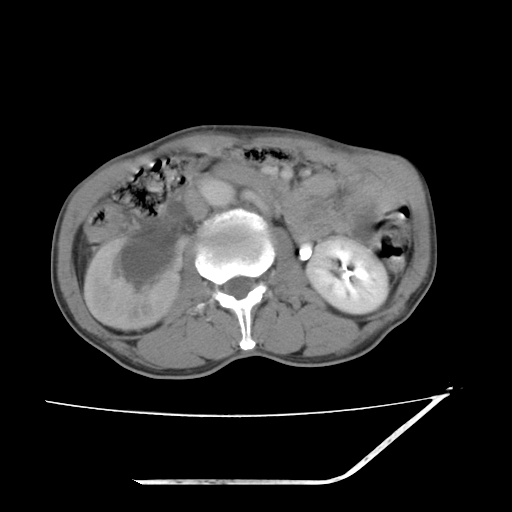

增强

考虑右肾盂癌,肾动脉受侵,右肾功能减退,右肾盂输尿管积水,管壁增厚,考虑种植转移,应该把下面扫完的

支持右侧肾盂癌伴肾静脉瘤栓形成可能性大,右肾结石.肝右叶后段低密度影,不除外转移.

右肾盂旁ca并肾静脉瘤栓形成/肾功能降低。

右肾结石。

右肾盂癌,肾动脉受侵,右肾盂输尿管积水,管壁增厚,考虑种植转移

右肾盂移行细胞癌并右输尿管中段转移.肾积水.

1.右侧肾盂癌伴肾盂积水。

2.肾脏功能减退,原因有:(1)肾动脉受侵。(2)肾静脉受侵(3)肾积水,等。本例,肾动脉显影较好,但受压明显;肾静脉无明显显示,受压或静脉癌栓,下腔静脉腔内未见明显充盈缺损。

3.右侧上段输尿管扩张,原因:(1)积水所致;(2)种植。